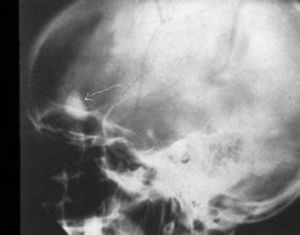

一、良性腫瘤

多以局部刮除植骨或切除為主,如能徹底去除,一般不復發,予後良好。

二、惡性腫瘤

治療上尚存在不少困難,儘管近年來採用所謂的綜合方法,療效有所提高,但仍遠遠不能令人滿意,在“挽救生命,最大限度保留肢體功能”的原則下,人們在積極地尋求更有效的方法。